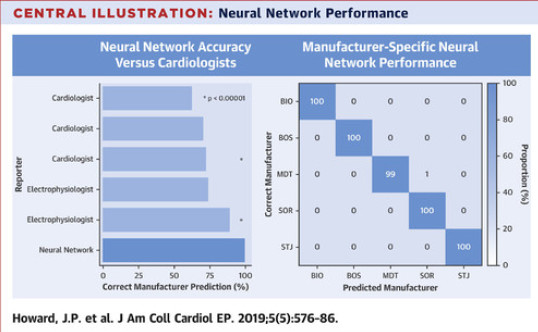

Pacemaker identification using neural networks - LINK

It's common for doctors to need to identify what model of pacemaker patients have during emergencies. James developed a free-to-use tool using AI which is able to accurately identify the model of pacemaker present on a chest X-ray, with far greater accuracy than that of a cardiologist.